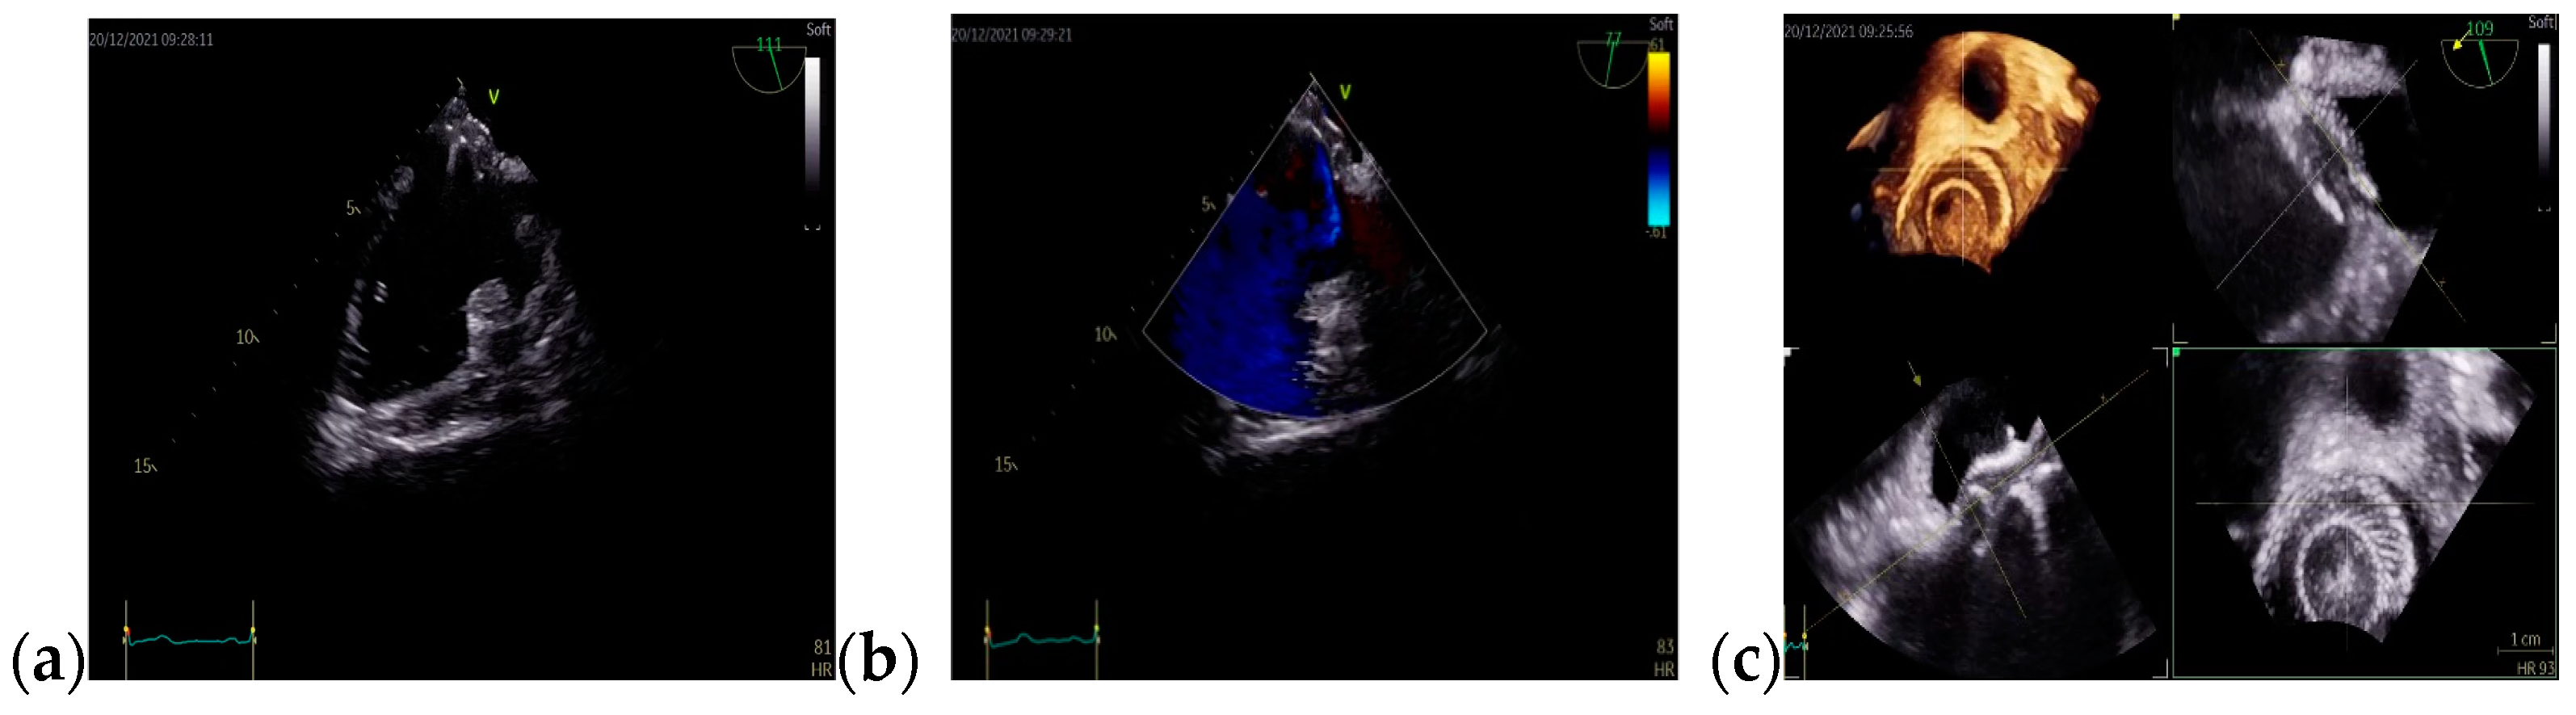

The patient’s symptomatology improved consistently in the immediate postoperative period. Four months later, the TOE revealed the Amplatzer occluder device located at the level of the interatrial septum, with no residual shunt (Figure 6).

Figure 6.

TOE: (a) Bicaval view: the Amplatzer occluder device (b) Mid-esophageal short-axis view: Amplatzer occluder device with no residual shunt (c) 3D TOE: Amplatzer occluder device; Abbreviations: TOE—transesophageal echocardiography.